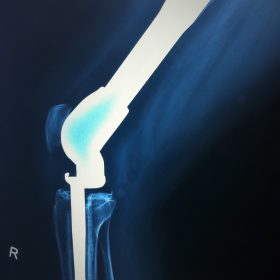

Σε αυτό το σημείο η Αρθροπλαστική Γονάτου αποτελεί μονόδρομο.